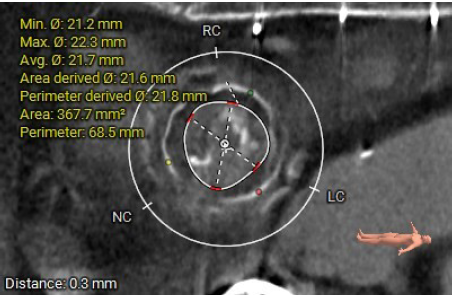

影像分析

生物瓣金属内径28.9mm

面积折算直径21.6mm

周长折算直径21.8mm